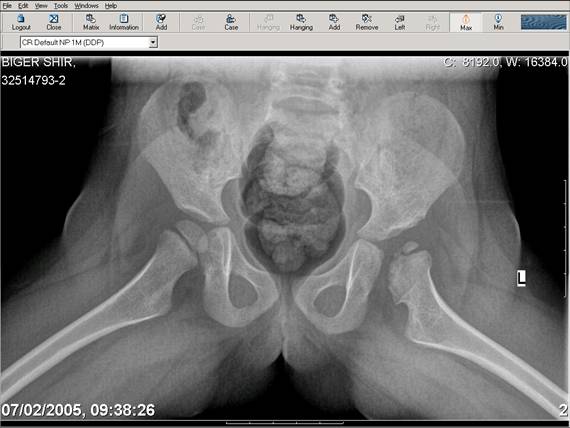

Navernoe Dega

Chto by ne byt goloslovnym posilau vam svoi sluchai gde sdelal vse chto napisal vyshe